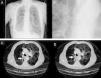

The level of anesthesia and vital signs are closely monitored throughout the procedure, and an X-ray is obtained after completion of valve placement (Fig. 3C and D) or computed tomography, if necessary, to rule out complications, confirm lung re-expansion and correct anchorage.

Images obtained after IBV valve placement (patient no. 8). (A) Chest X-ray with IBV valves in right upper lobe. (B) Detail of chest X-ray with IBV valves in right upper lobe. (C) Chest X-ray in patient with bullous emphysema and IBV valve in right B2 (indicated by the arrow). (D) Chest X-ray in patient with bullous emphysema and IBV valve in right B1 (indicated by the arrow).

Nine procedures were performed in 8 patients with PAL. The series consisted of 7 men and 1 woman, with a mean age of 68.5 years. All patients has significant comorbidities, including severe pulmonary emphysema in 7 patients, respiratory failure in 5, thrombopenia <20000 platelets per microliter in 1 and ischemic heart disease in 1 patient. In 6 patients, PAL occurred after development of a spontaneous pneumothorax secondary to underlying lung disease (Fig. 4A and B), after treatment-related pneumothorax in 1 and after anatomical resection of lung cancer in 1.